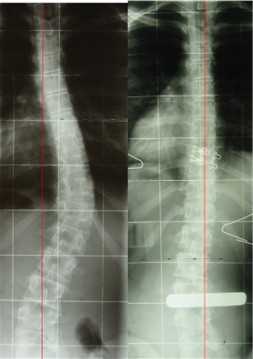

dr..... war nur ein beispiel, genauso läuft es oft in s... bei dr w.... oder auch anderswo.ein bild pack ich dir hier mal mit ein, bei dem mädel sollte auch ein neues korsett gemacht werden weil nach meinung von dr w... das aktuelle mist war. die patientin trägt immernoch ihr erstes korsett, also das schlechte. du siehst mit der qs ist das so eine sache. wer soll denn wen beurteilen? ich bin immer dafür, dass die kollegen sich mehr untereinander austauschen sollten und bei evtl. problemfällen ( wie auch immer begründet) sich auch mal helfen lassen sollten.

- Röntgenb..jpg (20.23 KiB) 11122 mal betrachtet